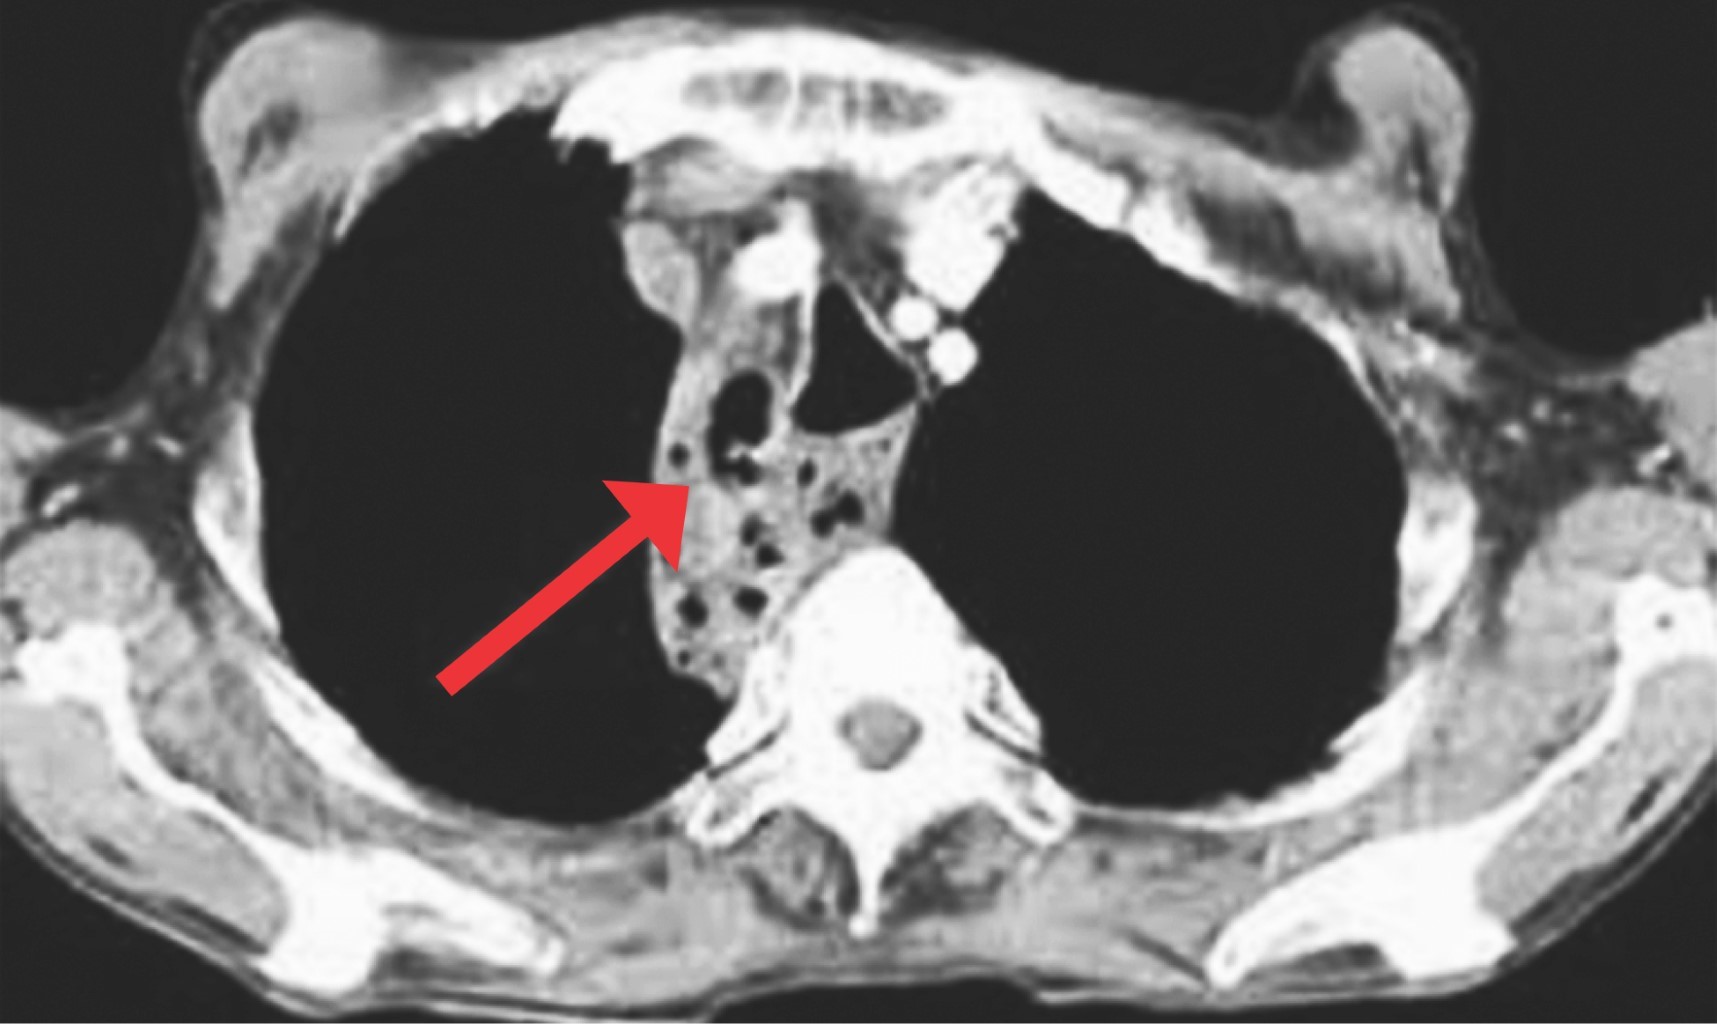

Dentro de las complicaciones derivadas de la discectomía se encuentra la fístula2 de líquido cefalorraquídeo, que si bien no es la más común,1-6 suele presentarse, y si es inadvertida puede derivar en complicaciones catastróficas o incluso fatales tal como la infección de tejidos blandos (Figura 1) y mediastinitis (Figura 2); todo esto debido a que, por la profundidad a la que se encuentra la columna respecto a la herida quirúrgica, es muy probable que no haya fuga de líquido tras la piel tal como sucede en las fístulas que se presentan en columna torácica, lumbar o cervical posterior. Esta condición anatómica originaría que pase totalmente inadvertida y el líquido cefalorraquídeo pueda permear sin obstáculos hacia las estructuras anatómicas anteroinferiores, y en este caso sería el mediastino anterior el receptor de este líquido.

Si este líquido cefalorraquídeo resulta infectado, originaría una infección de grandes dimensiones que puede ser catastrófica para el paciente.

A tres pacientes se les realizó resonancia magnética de columna cervical simple (Figuras 3, 4 y 5), los días de realización variaron debido a que dos de ellos se encontraban en institución pública y la accesibilidad a la resonancia magnética no pudo ser inmediata. En los tres se presentó una hiperintensidad con forma de flecha, la cual se localizaba en el espacio prevertebral y que llegaba hasta C1-C2 (Figuras 3, 4 y 5). La hiperintensidad era isointensa respecto al líquido cefalorraquídeo que se observaba en el conducto raquídeo. En uno de los casos se pudo documentar un trayecto fistuloso, pero no fue constante en ninguno.

En el primer caso se observa que el líquido se encontraba hacia arriba y hacia abajo del sitio operado y el grosor de la hiperintensidad prevertebral era sumamente grande y que había discreta migración hacia el mediastino, lo que orilló a tomar la decisión de reintervenir a la paciente inmediatamente para cierre de fístula. Esto podría considerarse un signo de fístula de alto gasto, sin embargo, no se cuenta con suficiente evidencia como para sustentarlo, haría falta más evidencia para poderlo determinar.